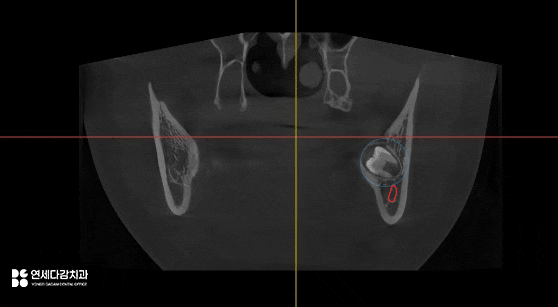

가락동 치과 에서 설명하는 케이스는

교합면이 혀쪽으로 향해 있으며,

진료 접근을 위해서는 잇몸 절개 후

골 삭제가 필요할 것으로 판단됩니다.

더불어, 아래쪽 매복 어금니 같은 경우

치근단 하방 하치조신경관과 근접할 때가 많아

사전에 정확한 거리 관계를 파악합니다.